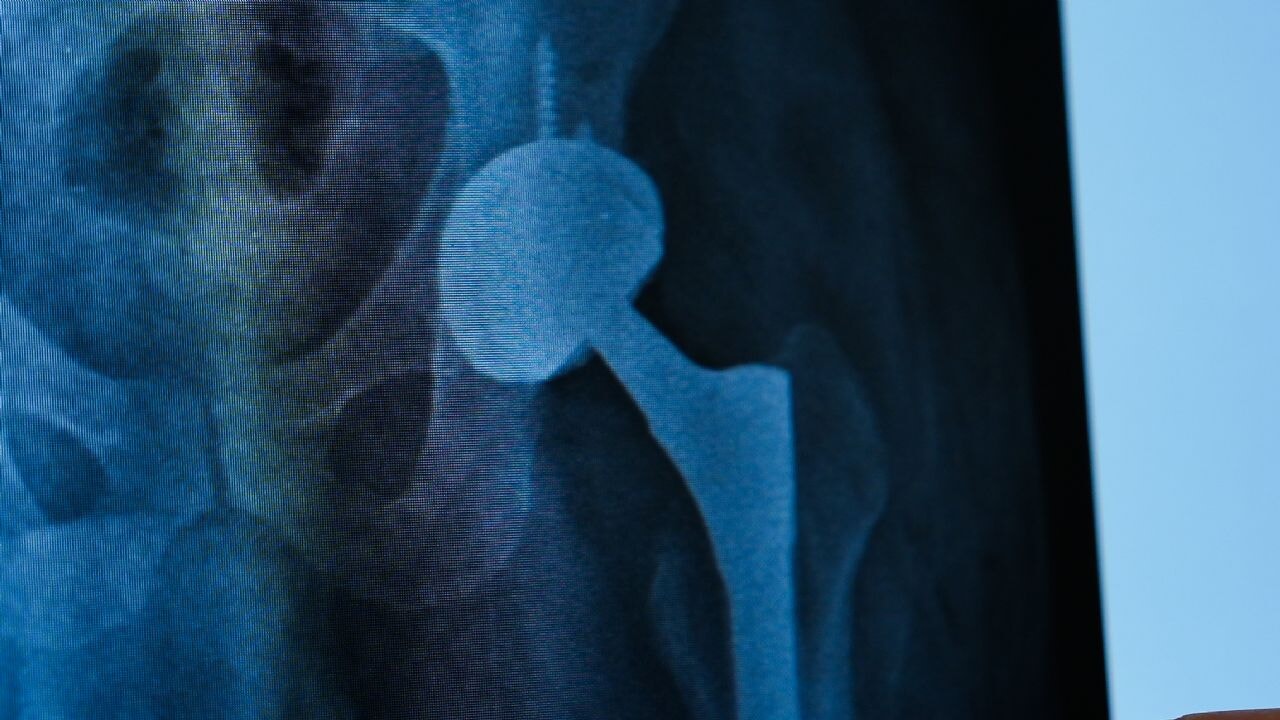

Tekirdağ Ergene’de yaşayan Zafer Aygün için iş kazası sonrası başlayan kalça ağrıları, dört yıl boyunca bitmek bilmeyen bir çileye dönüştü. Farklı hastanelerde ameliyatlar geçirmesine rağmen, kalça protezi etrafındaki enfeksiyon ve protezdeki gevşeme nedeniyle yaşam kalitesi her geçen gün daha da düştü. Aygün, aradığı çözümü Medipol Mega Üniversite Hastanesi’nde buldu. Ortopedi ve Travmatoloji Uzmanı Prof. Dr. İbrahim Azboy’un uyguladığı tek aşamalı kalça protezi değişimi yöntemiyle sağlığına kavuşarak hayatına kaldığı yerden devam etti.

Tedavi süreci hakkında detaylı bilgi veren Prof. Dr. İbrahim Azboy, “Hastamız daha önce protez ameliyatı olmuş ama protezin yerinden çıkması, ardından gevşeme ve çökme sorunları yaşamış. Bu komplikasyonlar üzerine ağrıları devam edince bize başvurdu. Enfeksiyon şüphesiyle yapılan ileri testlerde kalçada ayrıca enfeksiyon tespit ettik. Genelde bu tip durumlarda iki aşamalı cerrahi uygulanır. Bu yöntemde iki ameliyat yapılır. Protez çıkarıldıktan geçici olarak kalçaya çimento konur. İki ay sonra çimento çıkarılıp yeniden protez yerleştirilir. Ancak biz, Zafer beyin protez enfeksiyonunu ‘’Almanya’da geliştirilen tek aşamalı yöntemle tedavi ettik” dedi.

Prof Dr. Azboy sözlerine şöyle devam etti: “Önce enfekte protez çıkarıyor. Daha sonra mekanik debridman denilen yöntemle enfekte dokular etkili bir şekilde temizleniyor. Ardından kimyasal ajanlar kullanılarak iltihaplı bölge dezenfekte ediliyor. Yara geçici olarak kapatılıyor. Tüm setler ve malzemeler dışarı çıkarılıyor. Yeni setler açılıyor. Yeni protez aynı seansta hastaya yerleştiriliyor. Böylece tek ameliyatla hastanın enfeksiyonu tedavi edilmiş oluyor. Böylece hasta kısa sürede ayağa kalkabiliyor, hastanede yatış süresi kısalmış oluyor ve kalça fonksiyonlarını kısa sürede geri kazanıyor. Nitekim, Zafer Bey de ameliyat sonrası hızla yürümeye başladı ve hastaneden kendi aracına kullanarak taburcu oldu.”